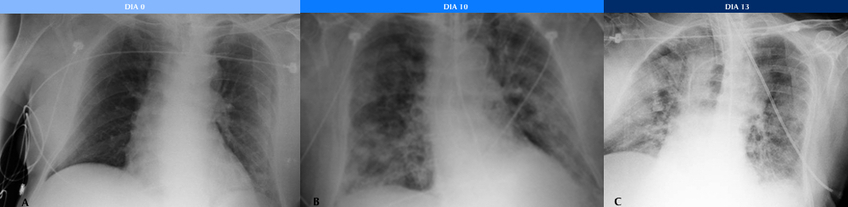

Se pudo estudiar la evolución radiológica de esta enfermedad en uno de los pacientes cuya evolución clínica fue tórpida, observándose en una radiografía inicial sutiles áreas parcheadas en vidrio esmerilado en campos pulmonares inferiores, las cuales fueron progresando hasta volverse coalescentes, difusas y consolidativas, llegando a afectar la mayor parte del parénquima pulmonar, asociándose además a derrame pleural. El paciente requirió intubación orotraqueal al décimo día de internación, sin lograr mejorar su cuadro clínico, y se constató su deceso 10 días más tarde (Fig. 2).

Jacobi et al. (13) estudiaron las manifestaciones radiológicas de la COVID-19 observadas con Rx portátil y describieron que en el momento en que los infiltrados involucran la mayor parte del parénquima pulmonar en forma difusa es cuando el paciente comienza con falla respiratoria y requiere intubación mecánica, lo que pudimos comprobar en nuestro trabajo.